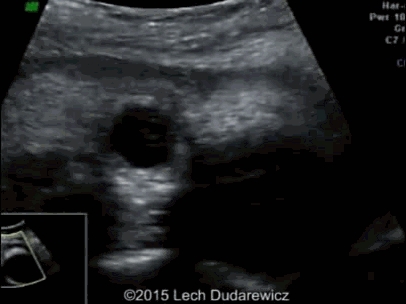

病例 3. 患者 22 岁,中期妊娠时超声检查有如下所见。

图像及动态视频均显示胎儿眼距过宽、单侧小眼畸形和双侧白内障

孕妇最终分娩一女婴,仅存活 9 天,经分子遗传学学确诊为 Yunis Varon 综合征。Yunis Varon 综合征可能是染色体 6q21 的 FIG4(609,390)基因位点的突变所致,发病率未知,但非常罕见,目前报道不足 20 例。